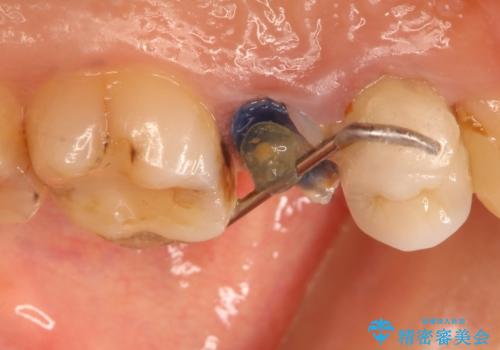

かぶせ物と詰めてある修復物を除去すると歯肉の中まで虫歯になっていました。

歯を部分矯正で引き上げて、虫歯を徹底的に取り除き、適合の良いかぶせ物を装着する計画としました。